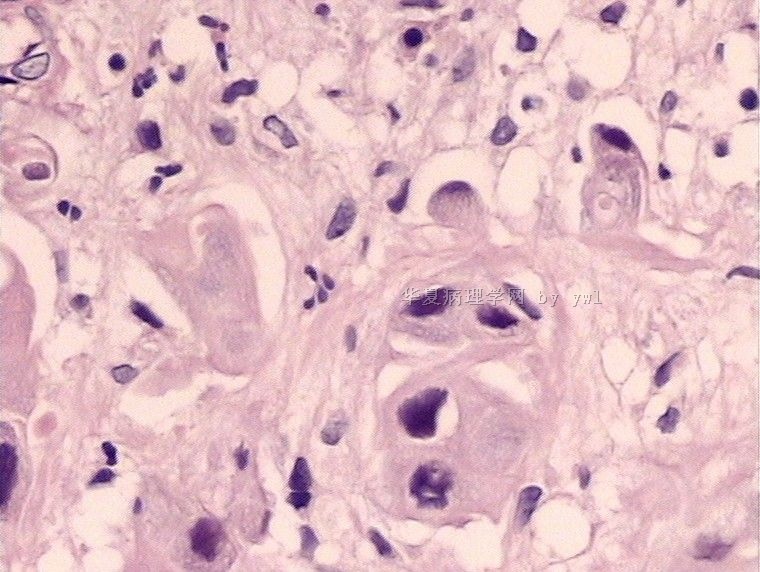

腺鳞癌?

姓    名: ××× 性别:   年龄:  39岁

标本名称:  宫颈活检

简要病史:  同房出血3次,tct HSIL

考虑:原位腺癌,小灶性区域有鳞状上皮向间质内浸润,考虑有鳞状细胞癌结构。